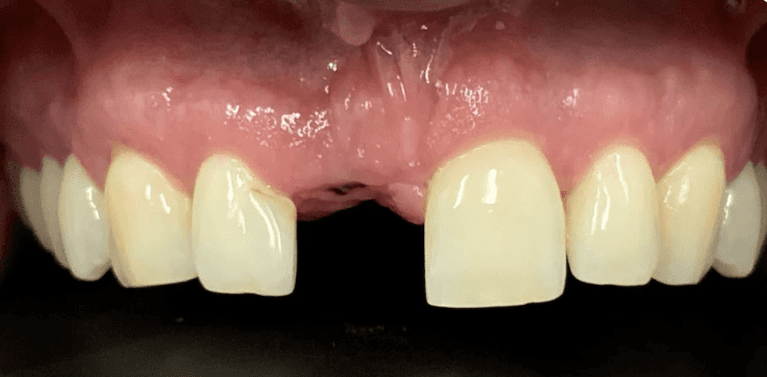

Upper All on 4 fixed implant teeth with Finals. Patient went home with fixed temp teeth the same day.